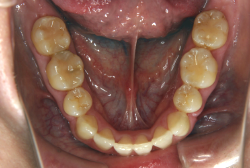

叢生(そうせい)

凸凹な歯並びのことを叢生といいます。矯正歯科に来院する患者様の主訴の中で、最も多いのが「配列の凸凹を真っ直ぐにしたい」というものです。歯の大きさと顎の大きさの調和がとれていないことが原因です。

凸凹を主体としたケースの場合、当院の平均治療期間は18ヶ月ですので、このケースは少し長めに経過しました。理由の一つは凸凹の程度がかなり重症だったと言うことですが、もう一つは、右下第2大臼歯が45度くらい前傾していたため、それを整直化させるために時間を要したと考えています。いずれにしても最終結果は大変よい状態と思います。

治療前は並びが乱れて見た目が悪いというのはもちろん問題ですが、歯科医学的に一番困るのは噛み合わせが悪いという点です。上下の犬歯(3番目の歯)は、上下的に離れた位置にあるため接触することができません。つまり歯としては存在していても、歯としては機能していないということです。